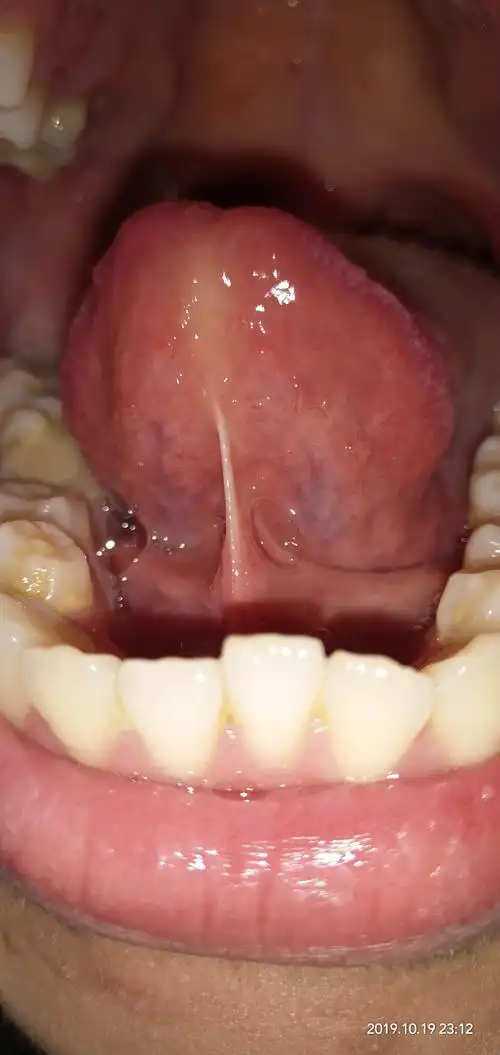

舌下静脉有异常吗

舌下络脉正常

舌下青筋是什么问题

舌下络脉短细,周围小络脉不明显,气血不足

舌下络脉粗大